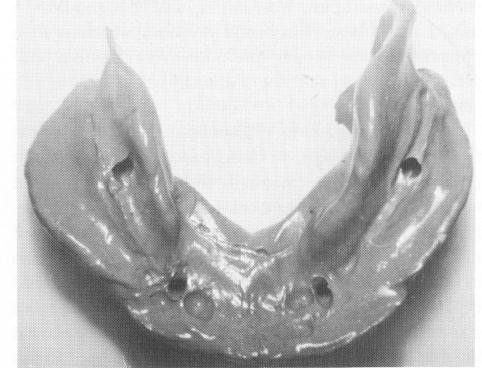

After about 3 to 6 weeks, the implant should have completely set and the surrounding tissues should be sufficiently healed to take the final "pick-up" impression for the final implant prosthesis (Fig. 12-32) . The superstructure framework is first placed over the four implant abutments (Fig. 12-33), and an accurate wax or stone occlusal record of centric relation is taken and the vertical dimension established (Fig. 12-34) . The superstructure is then picked up with one of the elastic impression materials (Fig. 12-35) or with one of the alginate materials (Fig. 12-36). All the soft tissue underneath the superstructure should be included in this impression. Instead of processing the denture, a wax-up of acrylic teeth fitted to the metallic superstructure should be tried during the next visit so that the bite, articulation, vertical dimension, and balancing of the case can be corrected (Fig. 12-37). Finally, the com-

Fig. 12-35. The superstructure framework is then "picked up" with an elastic impression.

Fig. 12-36. Sometimes an alginate impression is used to "pick up" the superstructure.